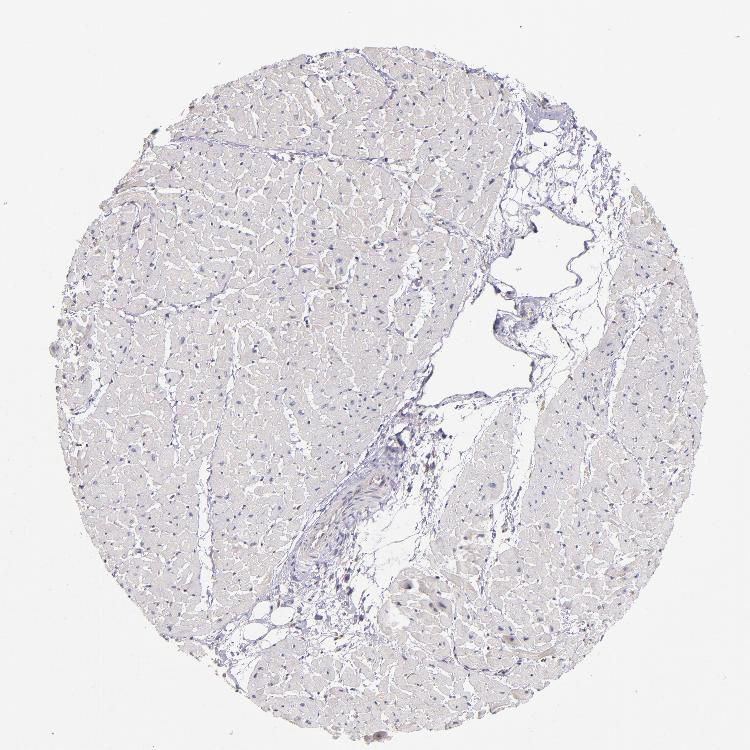

HEART MUSCLE - Antibody stainingi

Antibody staining in the annotated cell types in the current human tissue is reported as not detected, low, medium, or high, based on conventional immunohistochemistry profiling in selected tissues. This score is based on the combination of the staining intensity and fraction of stained cells.

Each image is clickable and will lead to virtual microscopy that enables deeper exploration of all samples and also displays staining intensity scores, fraction scores and subcellular localization as well as patient and tissue information for each sample.

Antibody HPA001619Antibody HPA002078

Cardiomyocytes Not detectedHigh